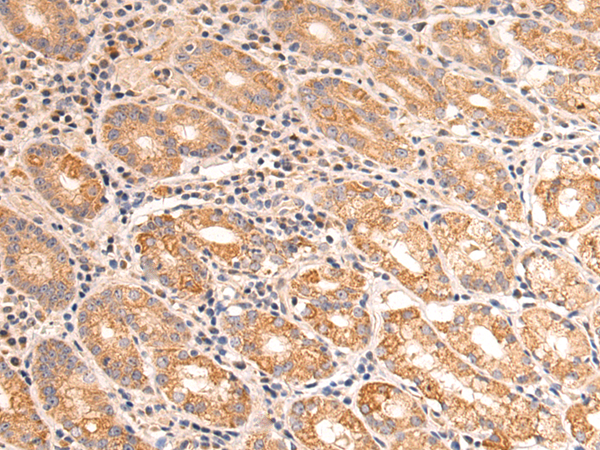

分类: 科研抗体货号: P10609别名: TRAP; CATC4; PCTAIRE2BP应用: IHC反应种属: Human, Mouse, Rat